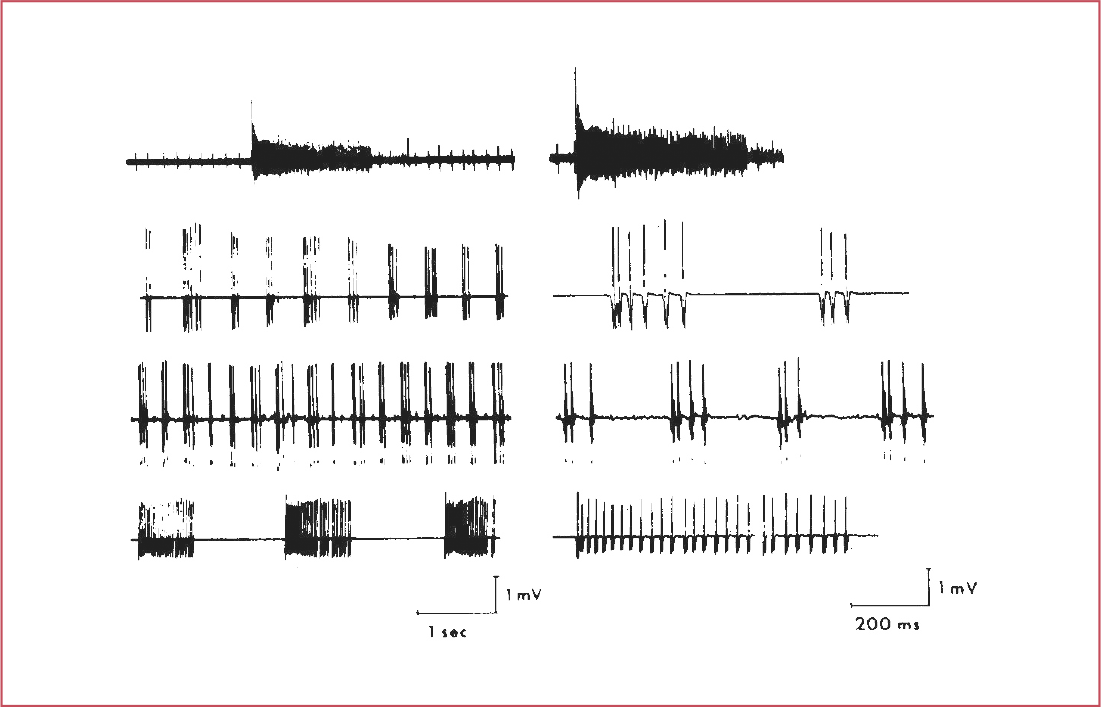

Normal duration, amplitude, and phases of a motor unit action potential?

- Duration: 5 - 15 ms

- Amplitude: up to 2 mV

- Phases: 2-4 (equal to # of baseline crossings + 1)